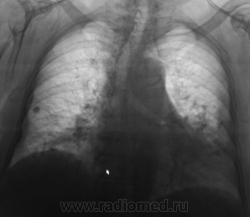

Второй срез.

Мы решили не затягивать диагностический процесс. Пациентка направлена к онкологам, по всей видимости, будет и КТ.